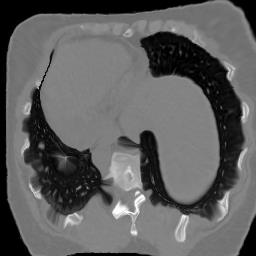

In clinical practice, well-aligned multi-modal images, such as Magnetic Resonance (MR) and Computed Tomography (CT), together can provide complementary information for image-guided therapies. Multi-modal image registration is essential for the accurate alignment of these multi-modal images. However, it remains a very challenging task due to complicated and unknown spatial correspondence between different modalities. In this paper, we propose a novel translation-based unsupervised deformable image registration approach to convert the multi-modal registration problem to a mono-modal one. Specifically, our approach incorporates a discriminator-free translation network to facilitate the training of the registration network and a patchwise contrastive loss to encourage the translation network to preserve object shapes. Furthermore, we propose to replace an adversarial loss, that is widely used in previous multi-modal image registration methods, with a pixel loss in order to integrate the output of translation into the target modality. This leads to an unsupervised method requiring no ground-truth deformation or pairs of aligned images for training. We evaluate four variants of our approach on the public Learn2Reg 2021 datasets \cite{hering2021learn2reg}. The experimental results demonstrate that the proposed architecture achieves state-of-the-art performance. Our code is available at https://github.com/heyblackC/DFMIR.